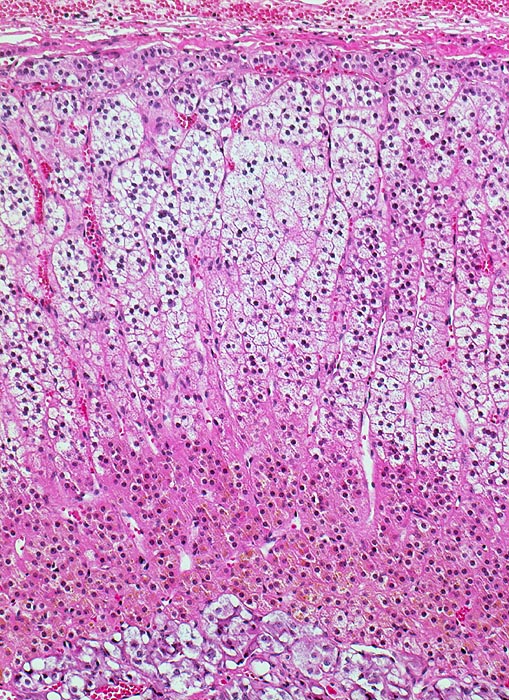

PathoPic – image database / PathoPic ID 4192 - normale Nebenniere

normale Nebenniere

Schichten der Nebenniere von oben nach unten:

Zona glomerulosa: kleine eosinophile Zellen mit dunklem Kern; Zellnester. Bildungsort für Mineralocorticoide.

Zona fasciculata: große, helle, schaumige Zellen radiär ausgerichtete, parallele Zellsäulen. Bildungsort für Glucocorticoide.

Zona reticularis: intensiv angefärbte, kleinere Zellen; netzartige Zellstränge (eher locker); bräunliches Lipofuscinpigment. Bildungsort für Sexualhormone.

Nebennierenmark: feingranulierte, polygonale Zelle; enge Zellnester; muskelstarke, weitlumige Venen (mit Längsmuskeln); evtl. multipolare Ganglienzellen (große Zelle + großer Kern)

Das kombinierte Gewicht beider Nebennieren bei gesunden Erwachsenen Frauen und Männern beträgt ca. 8g. Die Dicke der normalen Nebennierenrinde beträgt 1mm (0.7-1.3mm).